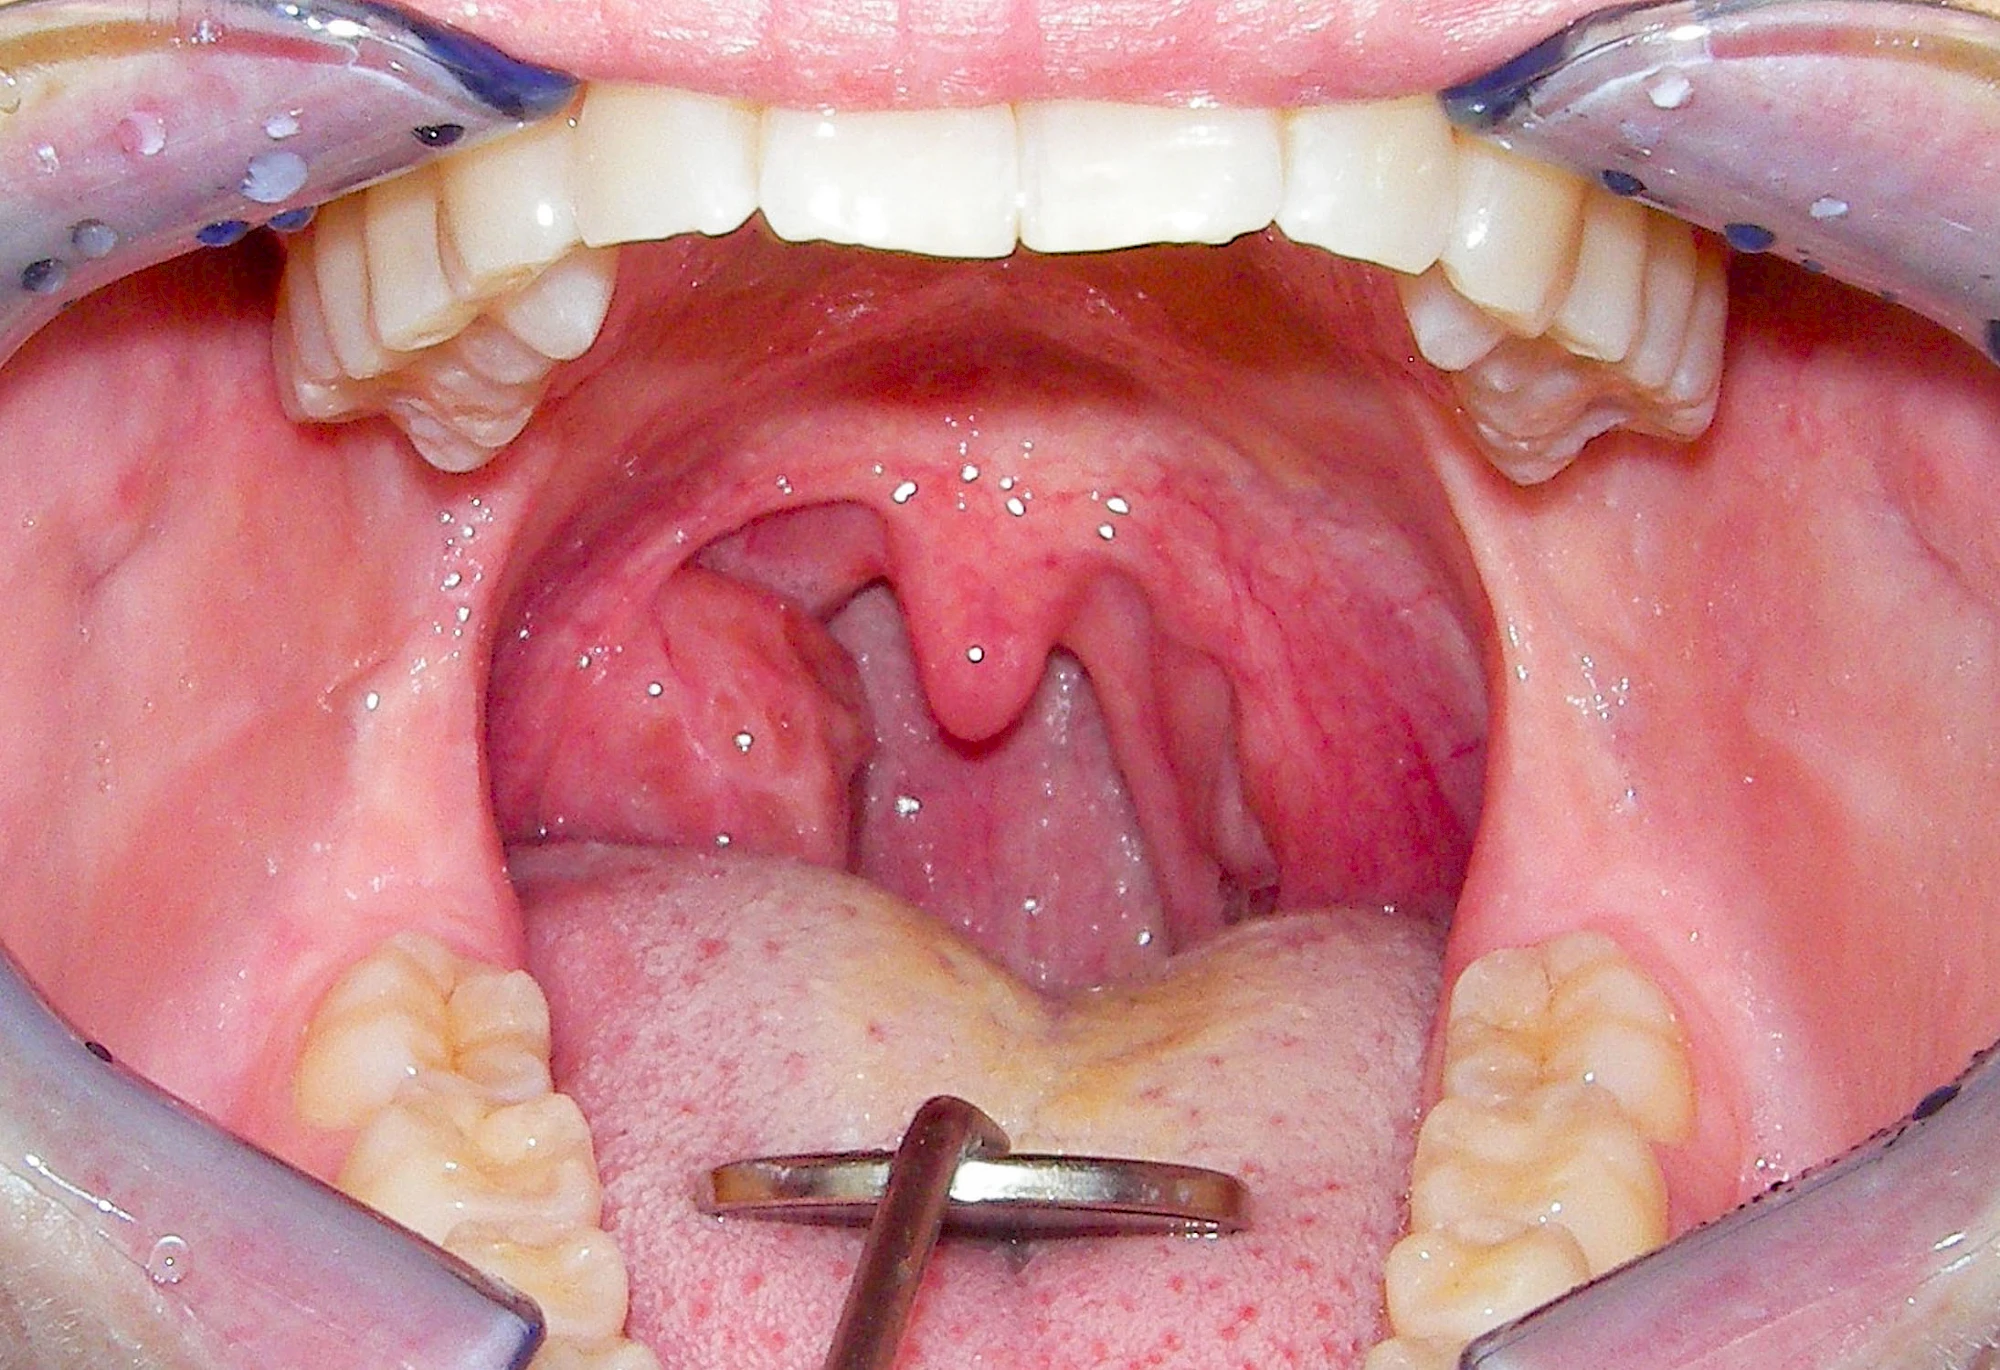

Mandelentzündung

Mandelentzündungen (Tonsillitis) zeigen häufig Rötungen, Schwellungen oder eitriges Sekret im Bereich der jeweiligen Mandel und sollten direkt ärztlich abgeklärt werden. Vielen Menschen wurde vor allem in der Kindheit ein- oder beidseitig die Mandeln entfernt, um die Atmung zu erleichtern. So können im Bereich der Gaumenbögen Vernarbungen oder Seitenunterschiede auffallen. Zudem können nach Mandelentfernungen (Tonsillektomie) die Infektanfälligkeit erhöht sein, da die Mandeln ja Bestandteil der Immunabwehr sind.

Bei Vergrößerung der Gaumenmandeln (Hyperplasie) z. B. infolge chronischer Entzündungenkann die Belüftung der Ohren gestört sein und es kann zu Schnarchen mit Atemaussetzern (Apnoe) sowie zu Schluckstörungen kommen. Bei entsprechenden Auffälligkeiten sollte eine ärztliche Abklärung erfolgen.